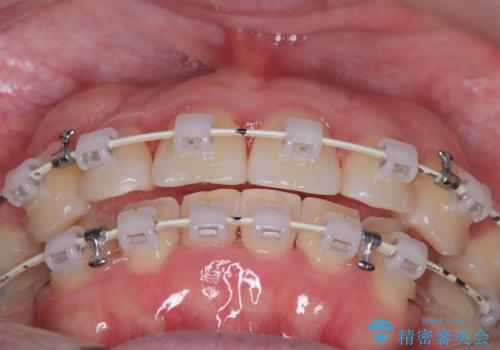

- 矯正装置

- 審美ワイヤー装置

- 患者様は、結婚式までに歯並びを整えたいとのご要望で来院されました。診断の結果、上下左右の第一小臼歯を抜歯し、歯列全体を整える計画としました。審美性を重視し、目立ちにくいホワイトワイヤーを使用した矯正を提案しました。治療期間は2年を目安とし、結婚式までに前歯の整列と噛み合わせを優先的に整えるスケジュールで進めました。定期的な調整と経過観察を通じて、計画的に治療を進めました。

結婚式までに仕上げるため、通常よりも細かく調整を行い、歯の動きを効率的に管理しました。審美ワイヤーを使用したことで、治療中も目立ちにくく、写真撮影などの日常生活での見た目の負担を軽減しました。抜歯部分のスペースを閉じる際には、前歯の位置や噛み合わせのバランスに配慮し、過度な力がかからないよう進めました。患者様の大切なイベントに間に合うよう治療計画を立て、理想的な仕上がりを実現しました。